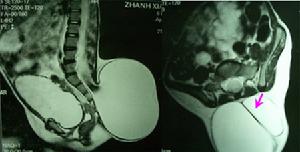

2.CT、MRI掃描顯示脊柱裂及脊髓、神經的畸形,以及局部粘連等病理情況。